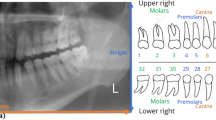

X-ray images are essential data sources for checking the condition of the teeth, gums, jaws, and bone structure of the mouth. Tooth recognition is fundamental in image-processing-based diagnoses. In most previous recognition studies, only four-axis-based object-detection models have been considered because they perform normal object detection while the object is resting on a flat surface. However, because the teeth have various orientations, the existing four-axis-based model leads to inaccurate and inefficient recognition results. Thus, in this study, we propose a five-axis-based object-detection model that considers the orientation of the tooth. Based on a tooth-image dataset labeled using the five-axis ground truth, our proposed method processed five-axis annotated data by employing a variant of the faster region-based convolutional neural network. In the experiment, our proposed method outperformed the existing four-axis approach, both qualitatively and quantitatively. The experimental results indicated that the proposed five-axis-based recognition model will be an important basis for a dental-image-based diagnosis.